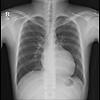

75세 남 폐성심(우심방비대)을 동반한 만성폐쇄성폐질환 환자 치료예

작성자

나인석

작성시간

14.04.24

조회수

721